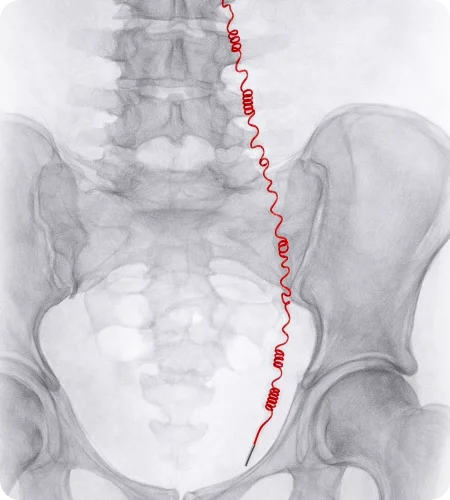

Uterine Artery Embolisation

Uterine artery embolisation is a minimally invasive treatment used to manage uterine fibroids and adenomyosis. The procedure works by blocking the blood supply to the affected tissue, helping reduce symptoms such as heavy bleeding and pelvic pain without the need for major surgery.